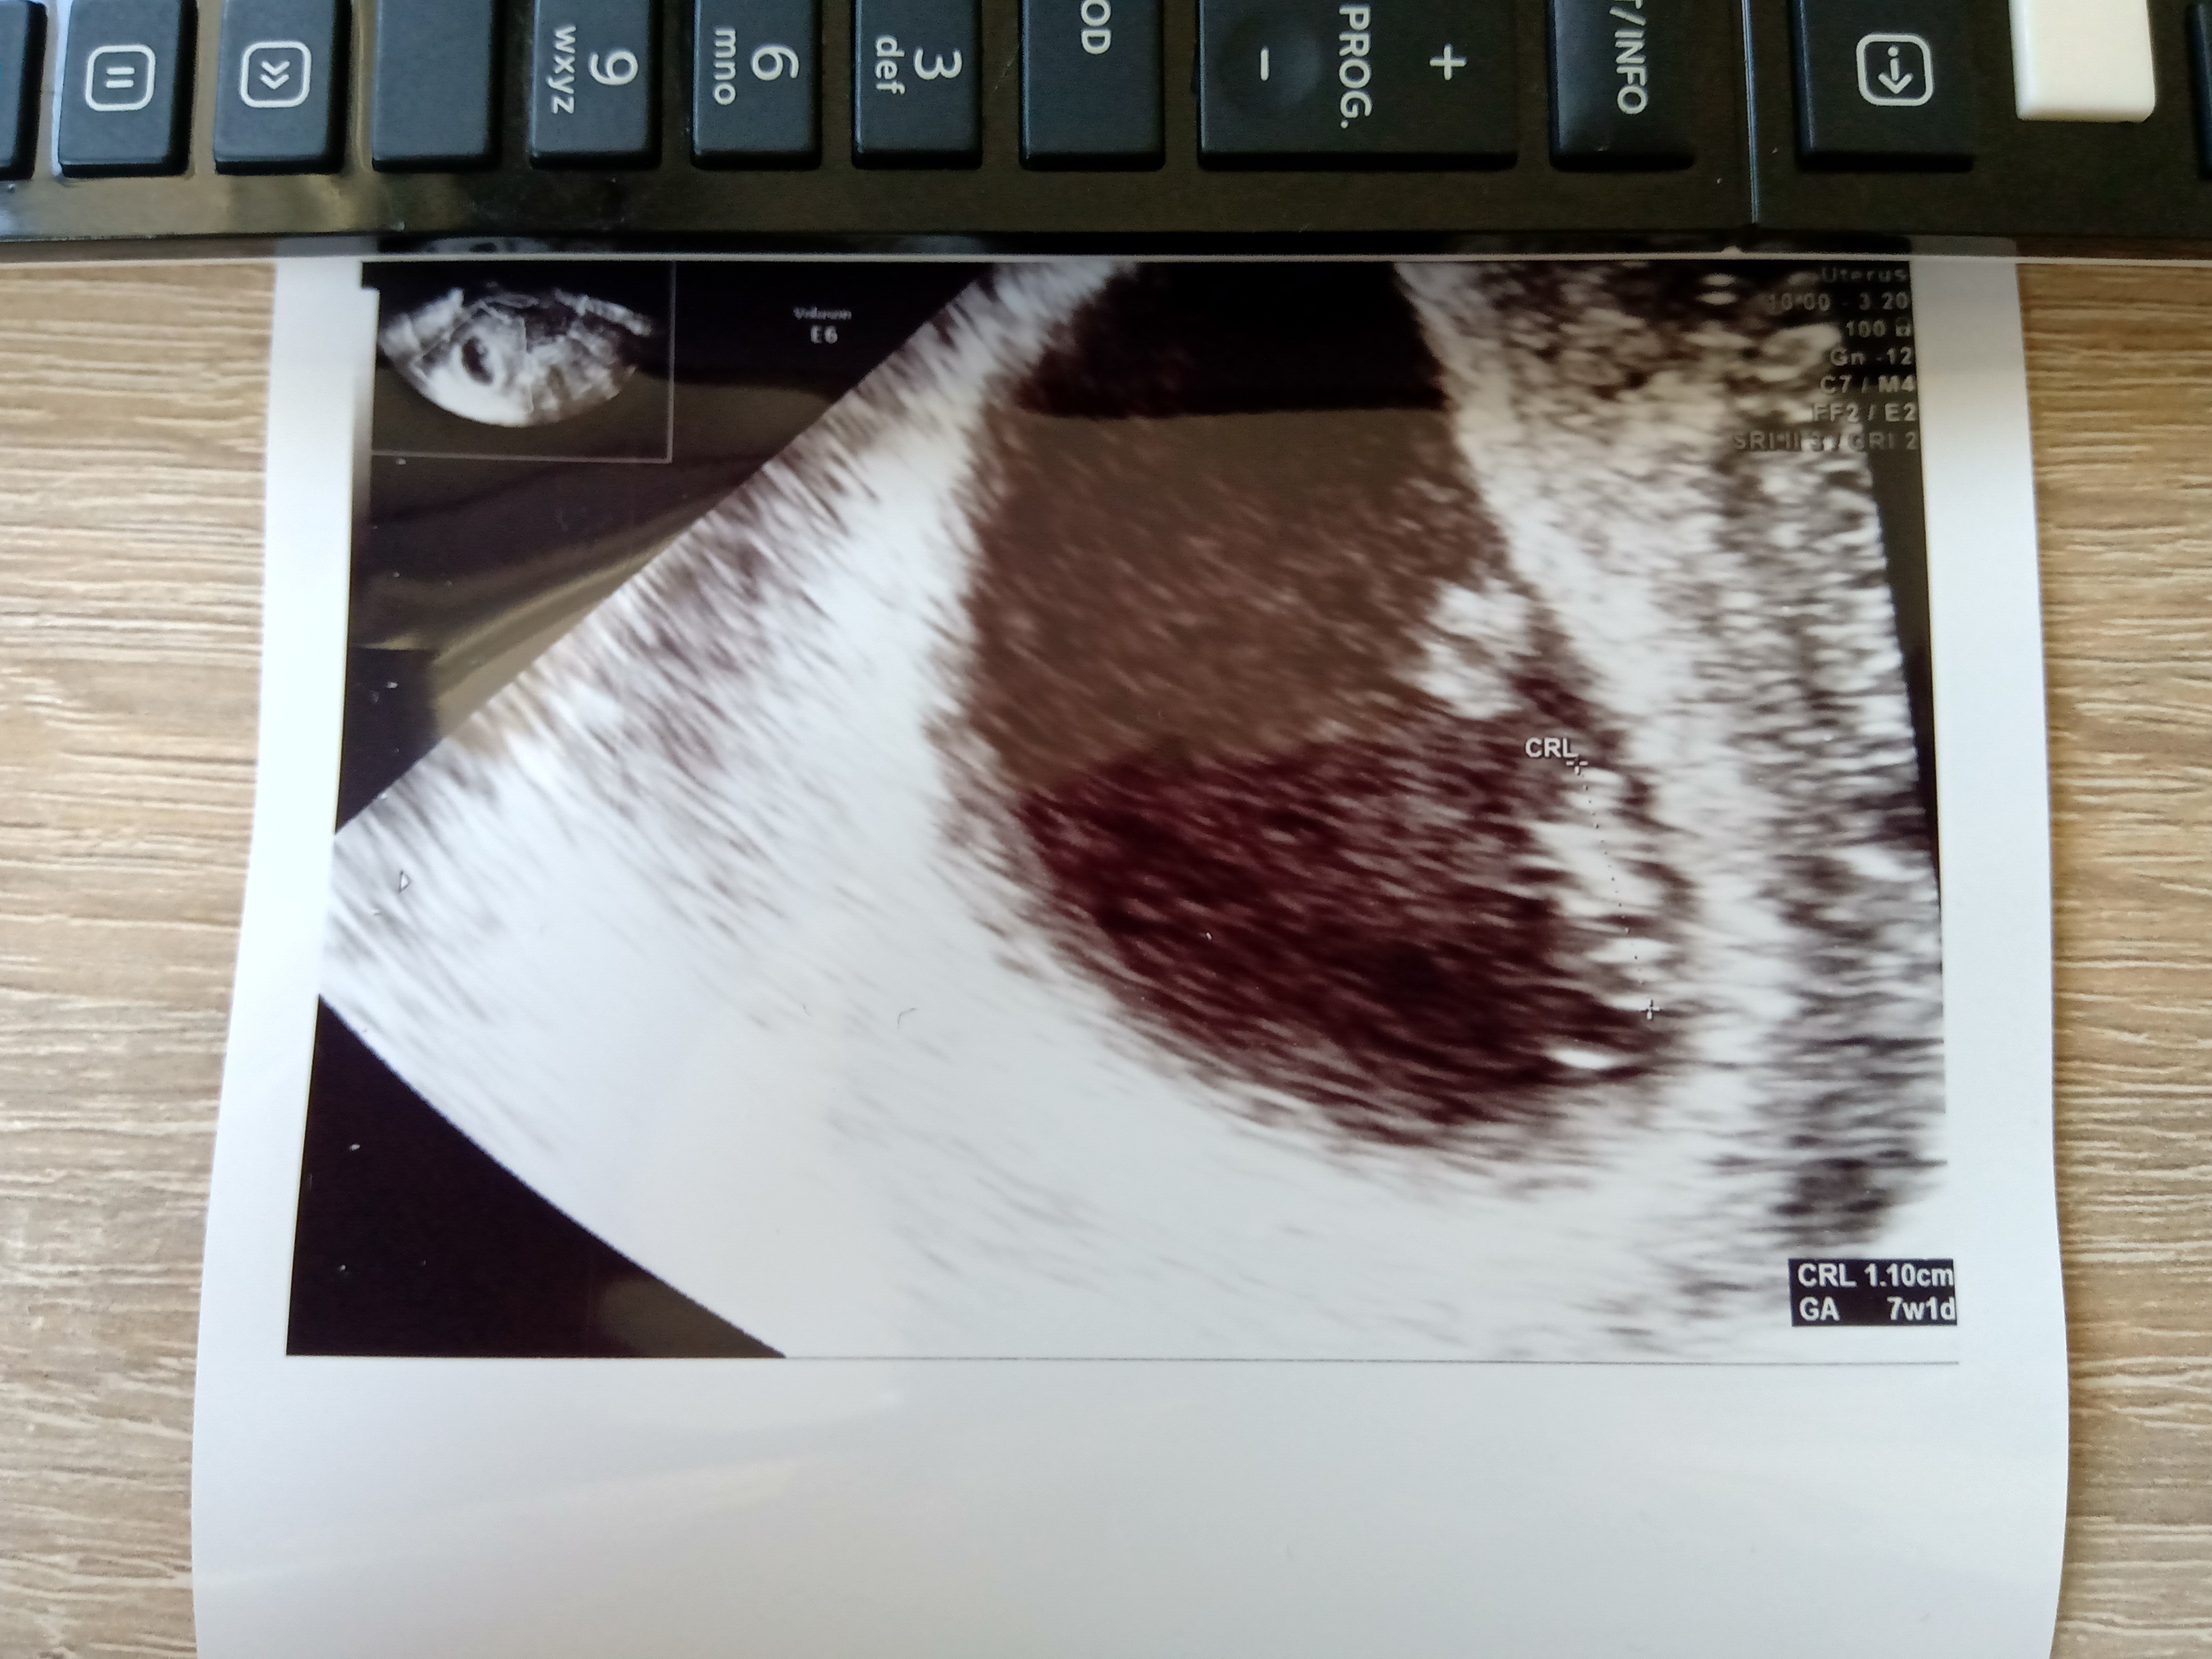

kochana a który masz tydz?Nie pochwaliłam się jeszcze wczorajszą wizytą. Więc serduszko jest, młode ma już 1cm wzrostu. Kolejna wizyta za 2 tygodnie. Wcześniej wyniki, ten cały "powitalny" zestaw za 300zł.

Zobacz załącznik 1162181

Dziś 7+3 wg. OM, wg usg wczoraj było 7+1 więc wszystko się zgadza.kochana a który masz tydz?![]()